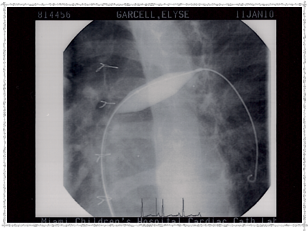

2010 - Pulmonary Artery Ballooned

Pulmonary Artery ballooned